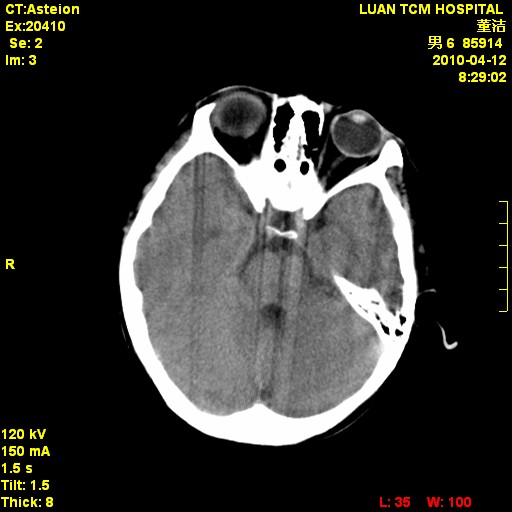

标题: PED3404:有结果,先猜猜这是啥病表现?男,12岁。 [打印本页]

标题: PED3404:有结果,先猜猜这是啥病表现?男,12岁。

考虑右侧额顶部颅内脑外血肿(edh可能)。

无病史无骨窗,无水肿无占位征象,右侧额顶部颅内血肿,或脑膜瘤。建议结合病史。

右侧额顶部自颅板向内近似半圆高密度影,周围无明显水肿,考虑:脑外血肿?脑膜瘤?淋巴瘤?